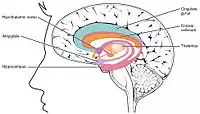

Hippocampus (lowest pink bulb) as part of the limbic system | |

The term limbic system was introduced in 1952 by Paul MacLean[12] to describe the set of structures that line the edge of the cortex (Latin limbus meaning border): These include the hippocampus, cingulate cortex, olfactory cortex, and amygdala. Paul MacLean later suggested that the limbic structures comprise the neural basis of emotion. The hippocampus is anatomically connected to parts of the brain that are involved with emotional behavior—the septum, the hypothalamic mammillary body, and the anterior nuclear complex in the thalamus, and is generally accepted to be part of the limbic system.[13]